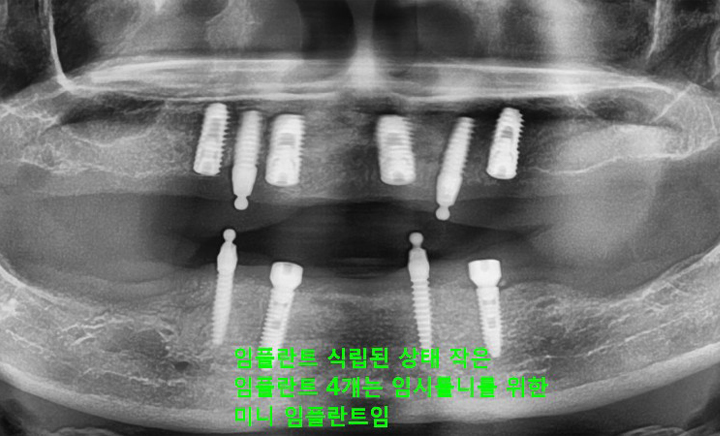

환자분 상태에 따라 임플란트를 2개에서 4개 정도만을 식립하고

그 위에 틀니를 고정시키는 치료 방법